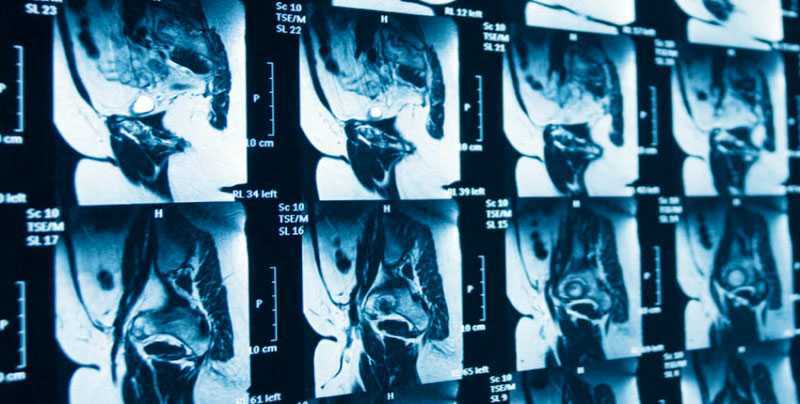

Используя метод магнитно-резонансной томографии, получаем детальные, высококонтрастные изображения внутренних органов и выявляем заболевания в самой начальной стадии развития. МРТ-изображения сохраняются в памяти аппарата, в электронном хранилище изображений клиники (PACS-система), могут переноситься на съемные носители (CD-диск, флэш-карта) или распечатываться на пленке специальным медицинским принтером.

Таким образом, ценность диагностической процедуры МРТ органов малого таза заключается в высокой информативности, естественной контрастности получаемых изображений, доступности, не инвазивности, безопасности и немногочисленности противопоказаний.

С помощью МРТ возможна диагностика большого количества заболеваний малого таза как у мужчин, так и у женщин. Информация о состоянии органов малого таза, полученная при МРТ, зачастую является основополагающей при формировании плана оперативного вмешательства, оценки послеоперационных изменений и мониторинга эффективности химио- или лучевого лечения.